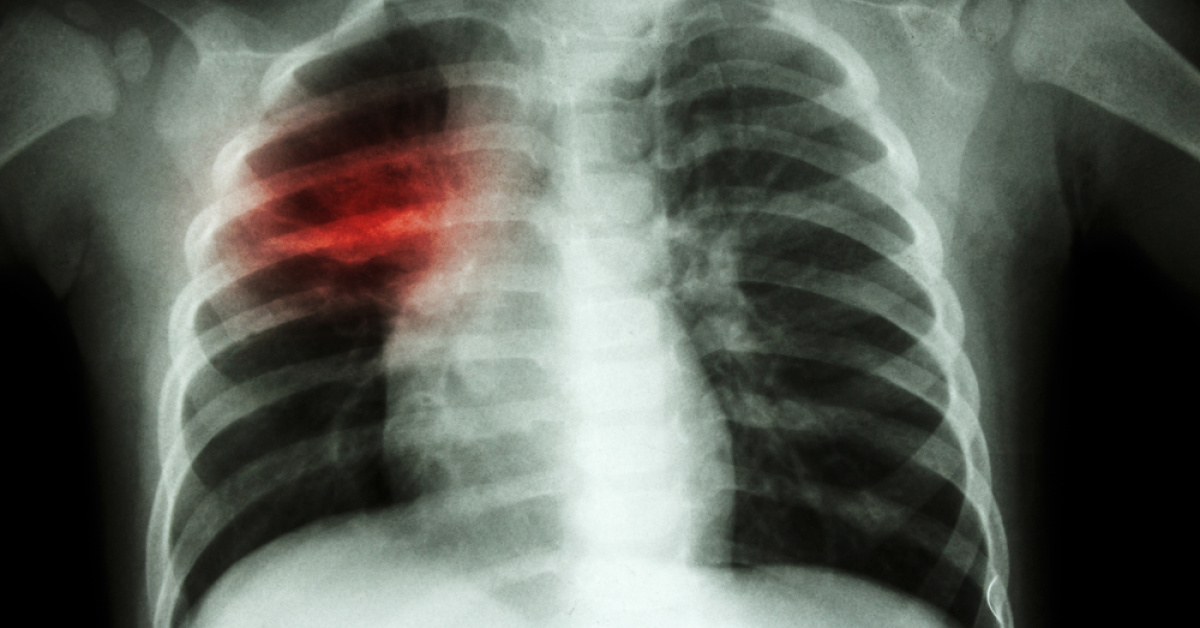

Kalp ameliyatının yalınce bedeni değil, nefis halini da tesirleyebildiğini söyleyen Kalp Damar Cerrahisi Uzmanı Prof. Dr. Cengiz Köksal, "Kalp ameliyatı yalınce bedeni değil, nefis halini da tesirleyebiliyor. Hastalar, ameliyatlar sonrası kendilerini tanımadıklarını ifadeleri ederken, yakınları da kişilik değişikliklerine şaşırabiliyor. Ameliyat sonrası ruhsal değişikliklerin olması normal olan tek şart ve bu süreç ruhsal yardımle daha sağlıklı yönetilebilir" dedi